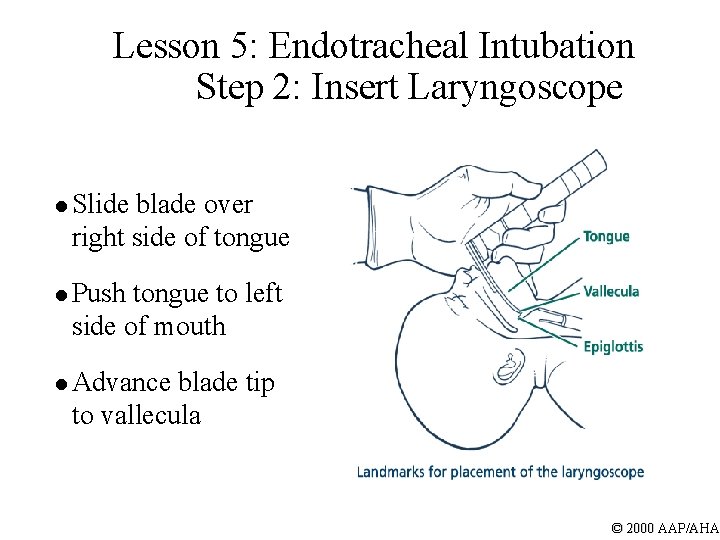

Lesson 5: Endotracheal Intubation Step 2: Insert Laryngoscope l Slide blade over right side of tongue l Push tongue to left side of mouth l Advance blade tip to vallecula © 2000 AAP/AHA